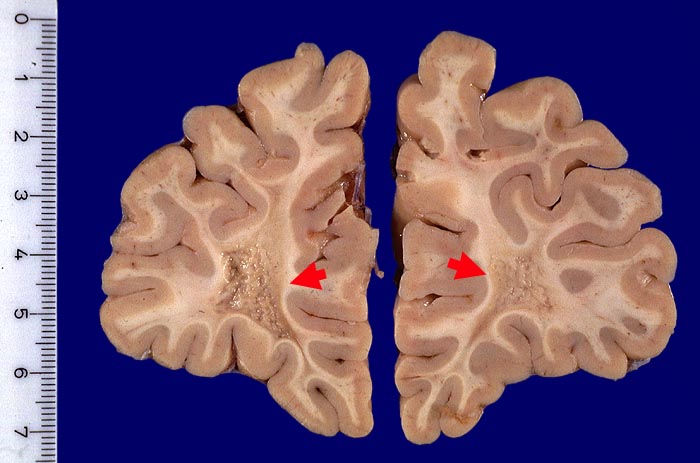

An Frontalschnitten durch das Gehirn fallen makroskopisch Entmarkungsherde vor allem im unmittelbar periventrikulären Marklager auf (um die Vorderhörner, die Cella media und um die Hinterhörner). Nicht selten finden sie sich auch um den Aquädukt und am Boden des 4. Ventrikels. Die Farbe der Herde hängt vom Alter des Prozesses ab (eher rosa bei frischen, eher grau bei alten Herden), die Konsistenz ist weich bei frischen, zunehmend derb bei alten Herden durch Gliafaservermehrung. Histologisch zeigen frische Entmarkungsherde in den ersten Tagen eine Oligodendrogliavermehrung. Ihr folgt mit beginnendem Markabbau eine Mikrogliareaktion. Mikrogliazellen, Monozyten und Makrophagen phagozytieren die Markscheidenzerfallsprodukte (> 10160) (> 10159), die teilweise lichtmikroskopisch im Zytoplasma erkennbar sind (> 10161). Lymphozyten und Plasmazellen sind vor allem perivenös an den Herdrändern lokalisiert. Zusätzlich proliferieren faserbildende Astrozyten (> 10162). In älteren Herden (vorliegendes Präparat) fehlen die Markscheiden praktisch vollständig. Axone bleiben erhalten und es besteht eine dichte Fasergliose. Diese ausgebrannten Herde überwiegen beim chronisch Erkrankten. Auch bei ihm können allenfalls noch frischere Stadien gefunden werden.

Morphologische Merkmale:

• Alter, scharf begrenzter Entmarkungsherd mit Verlust der blauen Myelinscheiden in der Holmes Luxol Färbung.

• Vollständiger Verlust der Markscheiden (fehlende blaue Farbe) bei erhaltenen Axonen (schwarze Fasern).

• Vereinzelte vorwiegend perivaskulär lokalisierte mononukleäre Entzündungszellen und mit Myelinbruchstücken beladene Makrophagen.

Makroskopie

Befund

Pathologischer Befund

Normalbefund